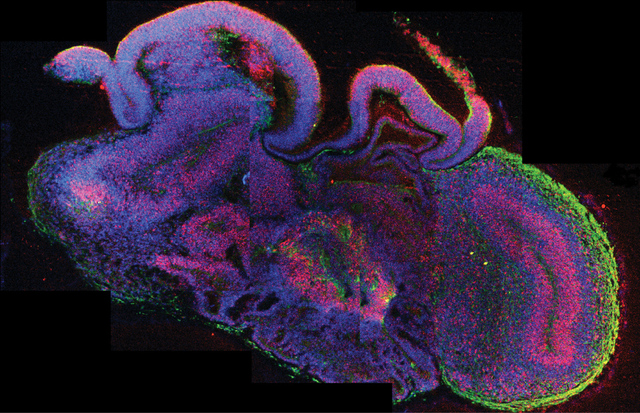

Γενετιστές στην Ιατρική Σχολή του Χάρβαρντ κατάφεραν να αλλάξουν τη γλώσσα στην οποία είναι γραμμένες οι γενετικές πληροφορίες ενός βακτηρίου, ένα επίτευγμα που θα μπορούσε να αξιοποιηθεί για την παραγωγή εντελώς νέων μορίων στη βιομηχανία βιοτεχνολογίας, ενώ ταυτόχρονα θα μπορούσε να εμποδίσει την απόδραση γενετικά τροποποιημένων οργανισμών.